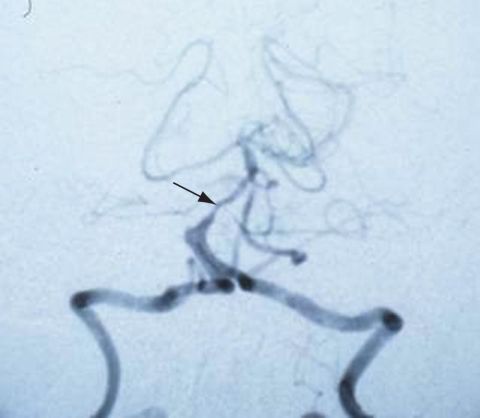

Imaging studies are generally not required to diagnose vertebrobasilar insufficiency; however, sometimes a CT scan may be performed to detect hemorrhages. An MRI may also be conducted to detect ischemic changes, and an MRA can be helpful to detect stenoses or occlusions. CT angiography is also useful in assessing vertebrobasilar vasculature.[16] (See Figure 1)